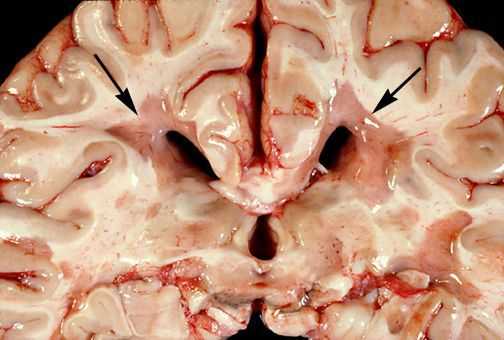

Для того, чтобы понять механизм развития РС, необходимо ознакомиться с патологической анатомией данного заболевания.

При микроскопическом исследовании обнаруживаются заметные и достаточно характерные изменения, выявляемые с наибольшим постоянством в спинном мозгу, мозговом стволе и полушариях головного мозга. Видны множественные бляшки различной величины (от точечных до весьма массивных, которые, к примеру, занимают весь поперечник спинного мозга), рассеянные преимущественно в белом веществе. Такая множественность и разбросанность очаговых изменений и определяет название болезни.

![Очаговые изменения в белом веществе мозга]()

Отдельные бляшки имеют округлую форму, они нередко сливаются и создают изменения сложных очертаний. Цвет бляшек на разрезе розовато-серый (недавно образовавшиеся очаги) или серый, желтоватый (старые очаги).

![Образовавшиеся бляшки]()

При разрезе бляшки определяется их большая плотность по сравлению с нормальной мозговой тканью. Эти уплотнения, склерозирование бляшек дало возможность охарактеризовать заболевание как склероз.

При микроскопии на первый план выступают изменения миелиновых волокон. В области очага, бляшки, в белом веществе наблюдаются в той или иной степени распад миелиновой оболочки, покрывающей нервные волокна центральных проводников, причём осевой цилиндр нередко остаётся неповреждённым.

![Распад миелиновой оболочки]()